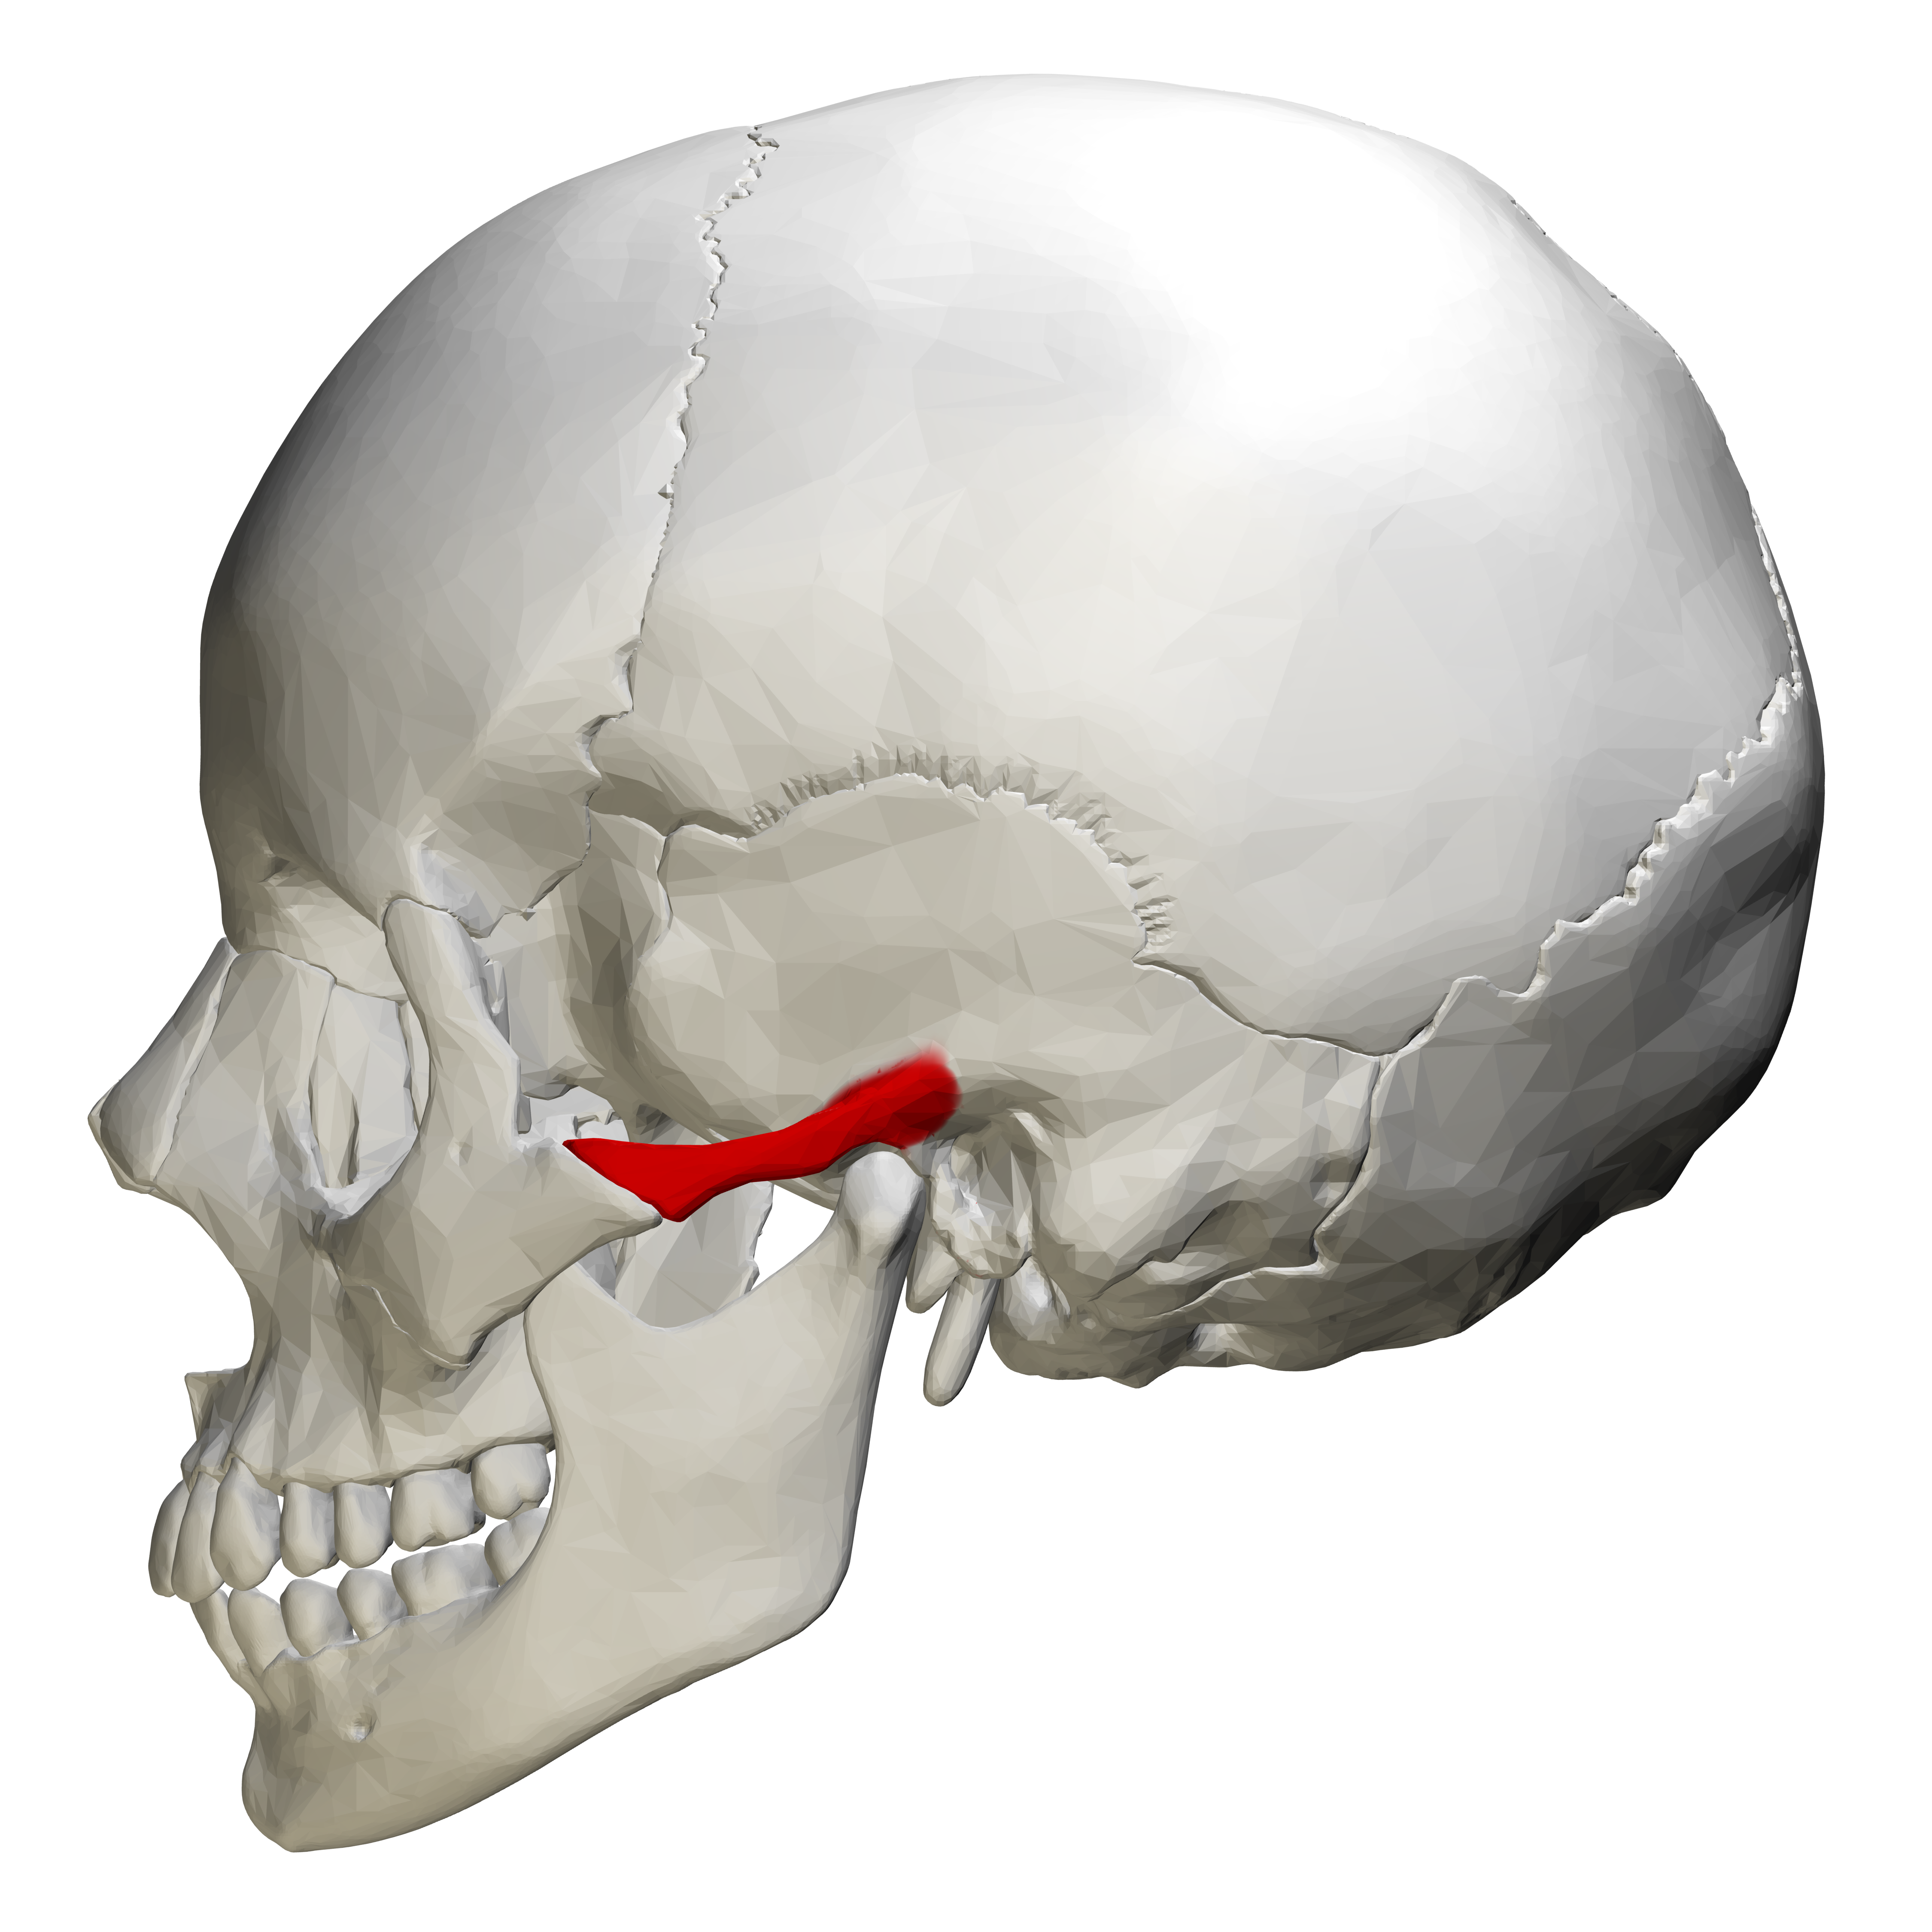

Анатомия детского черепа: Рентгеновские снимки и описание